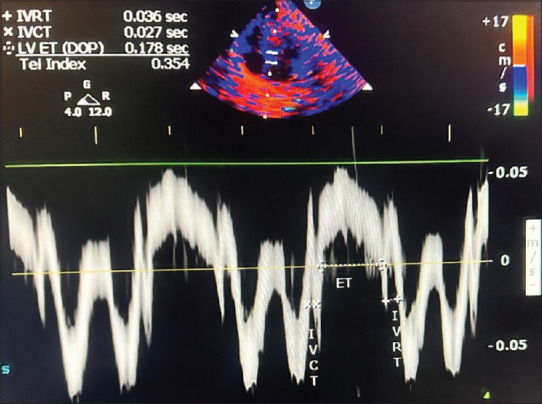

Methodology: The study was carried out in 92 neonates with a gestational age of more than 32 weeks who required invasive or noninvasive respiratory support. The tissue Doppler left ventricular MPI (LV MPI) was calculated before the initiation of respiratory support and after weaning from respiratory support. The data were analyzed using a paired t-test and a Wilcoxon signed-rank test.

Results: This study comprised 92 neonates with a median (interquartile range) LV MPI value of 0.56 (0.10) before initiation of respiratory support and 0.47 (0.04) after weaning from respiratory support with P < 0.001. The isovolumetric contraction time, isovolumetric relaxation time, and ejection time increased after weaning from respiratory support (all P < 0.0001). The severity of respiratory distress determined by invasive mode of ventilation and longer duration of respiratory support caused higher initial LV MPI before initiation of respiratory support compared with recovery and P < 0.001, suggesting subclinical ventricular dysfunction with respiratory distress in neonates.